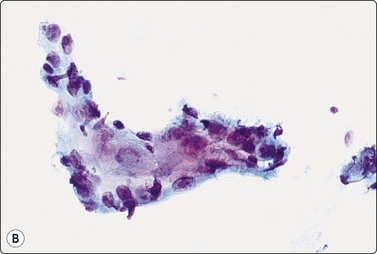

The cytology of nodular hidradenoma30-32 and of clear cell hidradenoma33,34 has been described in single cases. A benign skin adnexal tumor from our files, histologically reported as cystic eccrine hidradenoma, is shown in Figure 14.9. The FNB sample was of mucoid fluid which contained clusters of variably cohesive uniform epithelial cells with a moderate amount of cytoplasm and small dark ovoid nuclei. A dual population was not discernible. The cytology was reported as a benign skin adnexal tumor without further specification.

image image image

Fig. 14.9 Cystic eccrine hidradenoma

Loose clusters of basaloid cells with small, dark, uniform nuclei in a background of proteinaceous fluid (A, MGG; B, Pap, IP); (C) Corresponding tissue section (H&E, LP).

Page 374

Benign skin adnexal tumors located to the breast or axilla can be mistaken for primary or metastatic breast cancer.33,35 Knowledge of the exact localization of the lesion and its relation to the skin is essential when examining FNBs, as illustrated by the following case from our files:

A 60-year-old woman with a history of right mastectomy for cancer 4 years previously presented with a lump in the right axilla. It was described as subcutaneous by the surgeon who performed the FNB and the clinical diagnosis was metastasis of breast cancer. Smears were highly cellular, of epithelial cells both forming cohesive aggregates and dispersed as single cells. True papillary fragments were not seen. The cells had a moderate amount of dense cytoplasm and there was relatively mild nuclear atypia (Fig. 14.10). The pattern was considered to be in keeping with metastasis of a low-grade breast carcinoma. However, the nodule was, in fact, intracutaneous and the histology was reported as syringocystadenoma papilliferum (Fig. 14.10).36

Fig. 14.10 Syringocystadenoma papilliferum

Clustered and dispersed epithelial cells; moderate amount of cytoplasm; mildly atypical nuclei; no true papillary fragments (A, MGG, HP; B, H&E, IP); (C) Corresponding tissue section (H&E, LP).